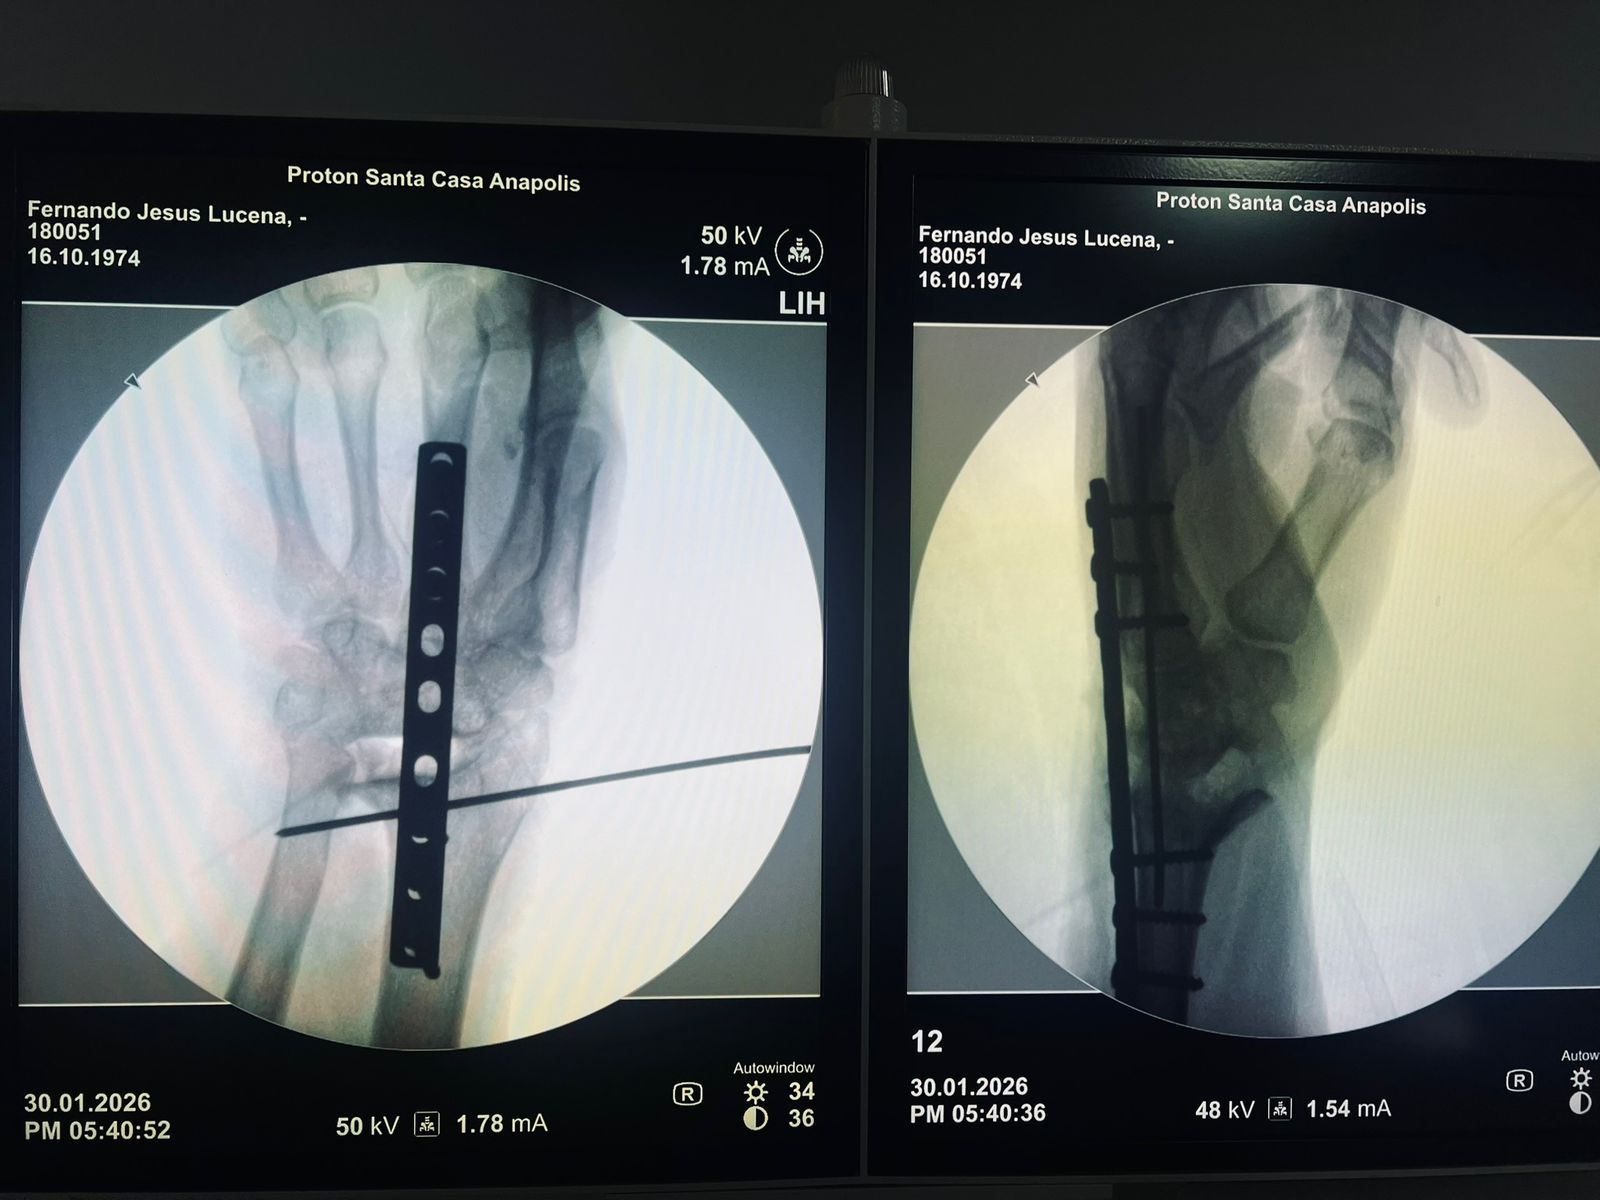

Essa transformação não está apenas nos números. Ela pode ser vista. As imagens que acompanham este texto mostram dois casos atendidos hoje no pronto socorro: crianças com fraturas no antebraço que foram avaliadas, diagnosticadas e operadas no próprio hospital, sem necessidade de transferência. Situações que exigem agilidade, equipe treinada e estrutura funcional.